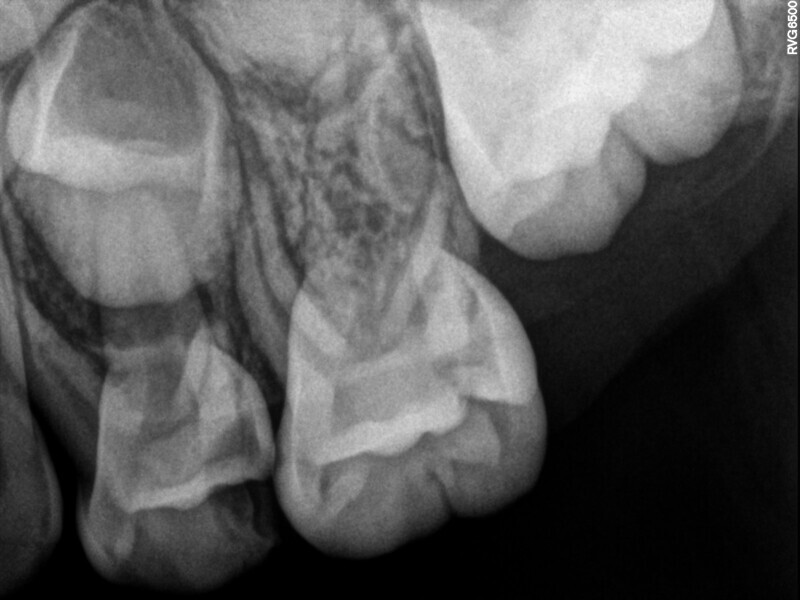

Cas 3 (Figs. 10 à 13)

Ce patient âgé de 7 ans présentait une douleur légère depuis plusieurs jours. L’examen a montré une lésion cavitaire étendue et profonde dans la première molaire temporaire inférieure gauche. La gencive ne présentait aucun gonflement, mais la dent était douloureuse à la percussion. La radiographie a confirmé la gravité de la carie, mais n’a révélé aucun signe correspondant à une modification de l’os environnant. Une pulpectomie était le traitement de choix. Le diagnostic de nécrose pulpaire a été confirmé après la préparation de la cavité d’accès et l’identification de trois canaux qui ont alors été complètement négociés.Lors d’un second rendez-vous, 15 jours plus tard, la dent était totalement asymptomatique et elle a été restaurée au moyen d’une couronne en acier inoxydable. À la visite de suivi à 36 mois, la dent présentait une fonction normale et était totalement saine.